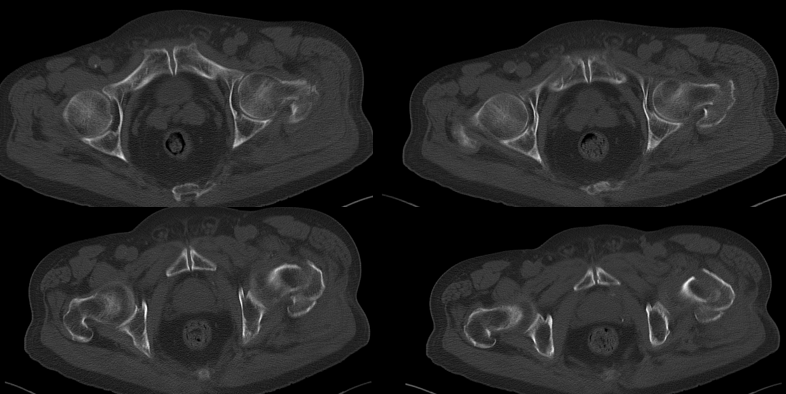

患 者:邱某,男,79岁。

主 诉:因撞伤致左髋部疼痛、活动受限30分钟,入院治疗。

症 见:患者自诉被小货车撞伤,致左髋部肿痛伴活动受限,受伤当时患者无昏迷、晕厥,无恶心、呕吐,无胸闷、气促,受伤后来入院就诊。

查 体:T:36.7℃,P:52次/分,R:20次/分,BP:130/74mmHg。

专科检查:神志清楚,检查合作,左髋部稍肿胀,皮肤粘膜完整,局部皮色淤青,左下肢外旋、未见明显短缩,左髋局部压痛,左足底叩击痛,左髋关节主动伸屈、外展、内收等活动受限;左下肢末梢皮色红润,感觉良好。

影像资料:

骨盆正位

髋部CT

髋部CT+骨三维

诊 断:

左股骨粗隆骨折,伴心动过缓,三度房室传导阻滞。阿托品试验阴性。